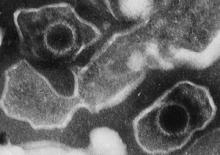

Actualité publiée il y a 10 années 2 moisLYMPHOME associé au virus d'Epstein-Barr: Une nouvelle immunothérapie adoptive